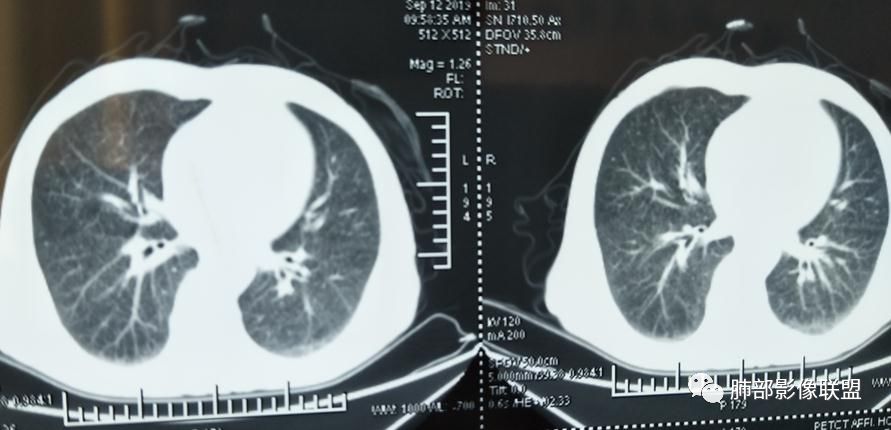

2019-10-20复查CT如下:

8月份就有弥漫细小结节

9月外院片也有弥漫细小结节

左上纵隔旁病灶存在

大小、分布均匀,边缘清楚

细小结节,弥漫,撒米粒样——血道来源

还是支持结核

血道来源的病灶,均匀、细微,而且部分有分支状,都符合粟粒型肺结核

鉴别转移瘤,太细微、太均匀,而且8~11月,会增大

10月20日的CT其实是抗痨治疗近1月复查的CT。患者来我院后抗痨治疗体温下降,症状明显好转。